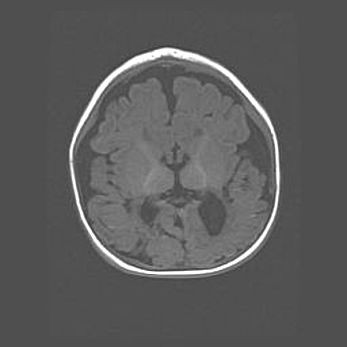

Открытая гидроцефалия.

Возраст: 9 месяцев 12 дней

Вес: 6800 г

Пол: мужской

Окружность головы: 41,5 см

Срок гестации: 28 недель

Гидроцефалия головного мозга у новорожденных имеет характерный признак: опережающий рост окружности головы приводит к визуально хорошо определяемой гидроцефальной форме сильно увеличенного в объёме черепа. Детские неврологи определяют следующие симптомы гидроцефалии у грудничков: выбухающий напряжённый родничок, частое запрокидывание головы, смещение глазных яблок к низу.